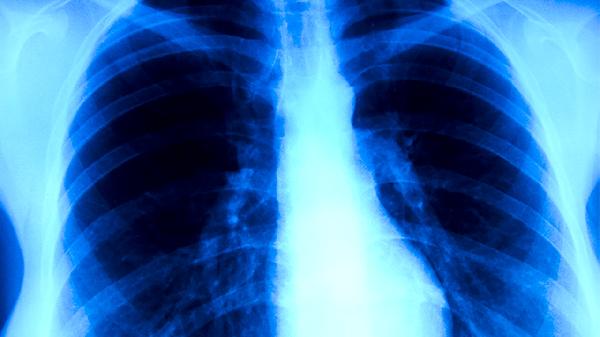

急性支原体肺炎的症状有哪些

急性支原体肺炎的症状主要有发热、咳嗽、咽痛、胸痛、乏力等。急性支原体肺炎是由肺炎支原体感染引起的呼吸道疾病,多见于儿童和青少年,部分患者可能伴随头痛、肌肉酸痛等全身症状。